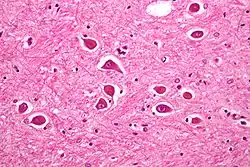

Micrograph of Alzheimer type II astrocytes, as may be seen in hepatic encephalopathy